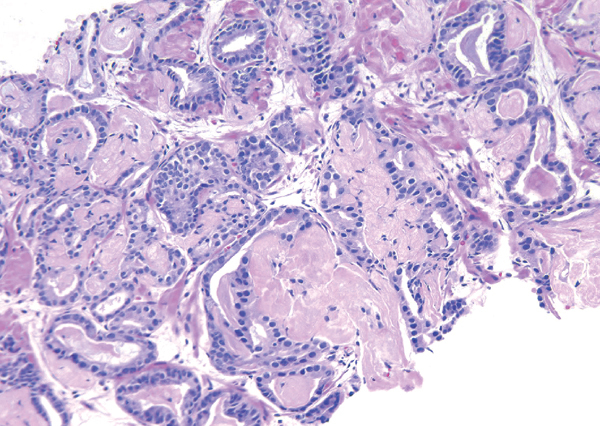

The stroma surrounding the neoplastic glands may show a combination of hypercellularity and deposition of a basophilic ground substance (‘mucinous fibroplasia’ or ‘collagenous micronodules’)